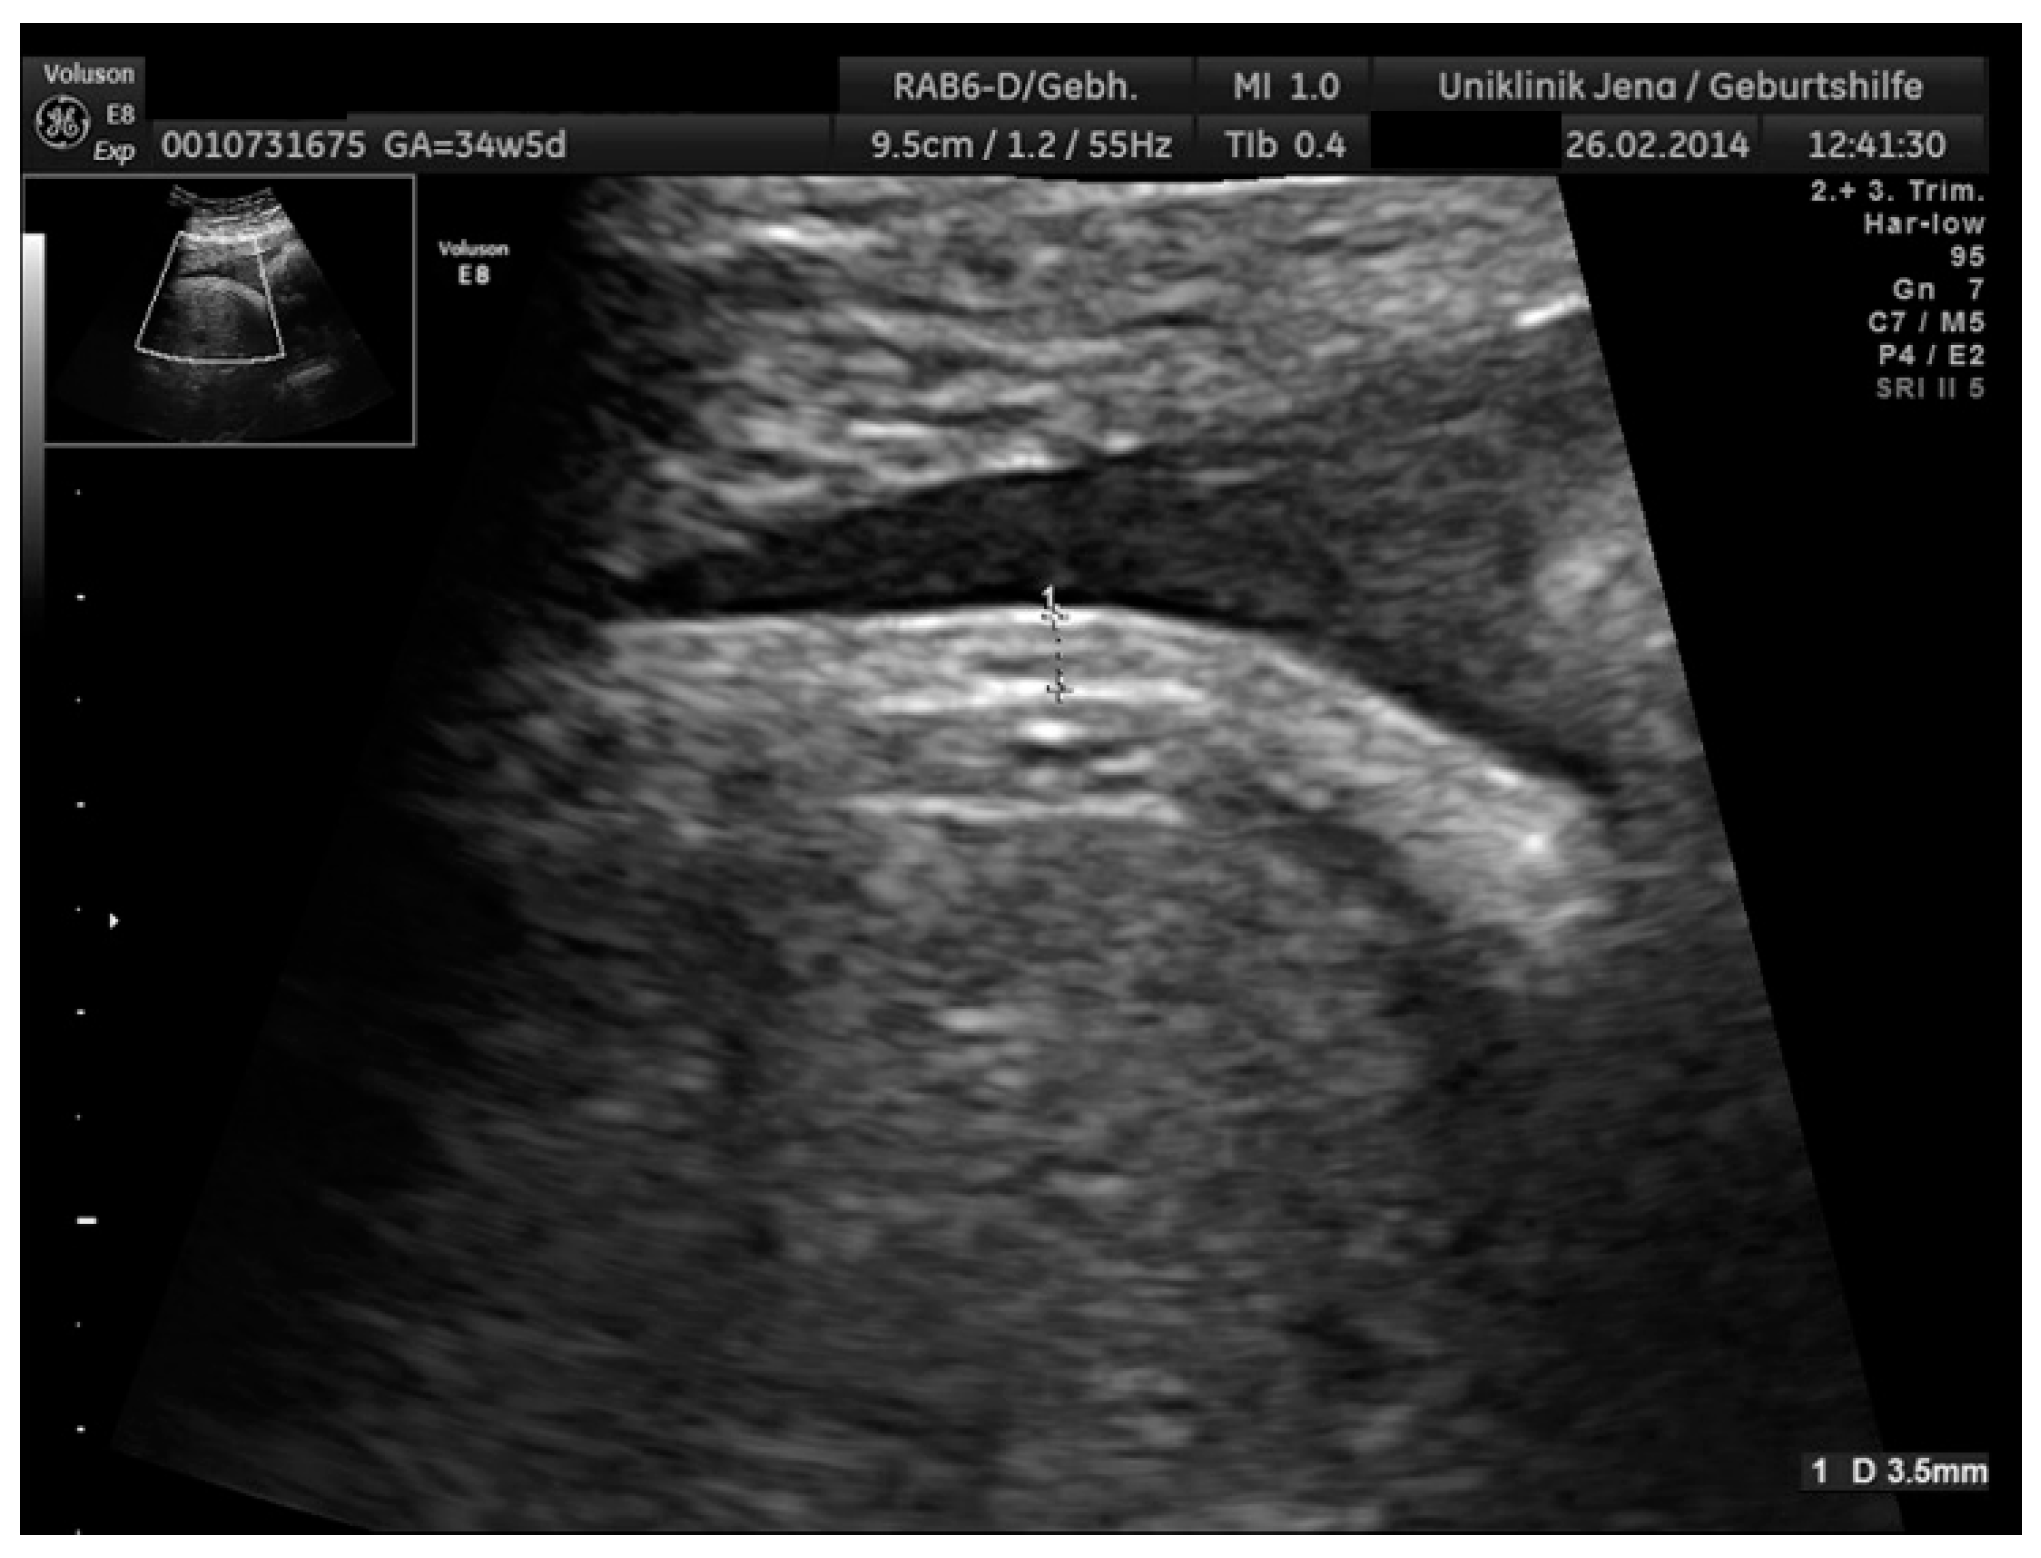

2.2. Ultrasound Parameters